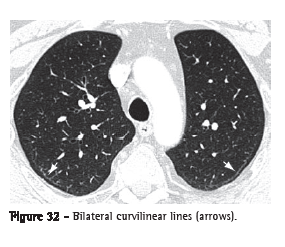

Subpleural curvilinear line (linha curvilínea subpleural)The subpleural curvilinear line is a curvilinear opacity of 1-3 mm in thickness, located in the subpleural region and having a parallel distribution over the pleural surface (Figure 32). It is a nonspecific sign for atelectasis, edema, fibrosis or inflammation.(3,7)